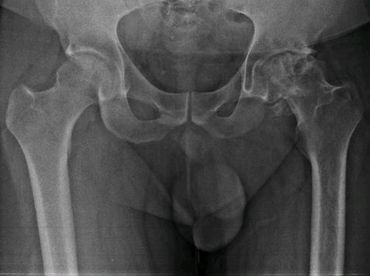

Artroplastía total de cadera no cementada izquierda